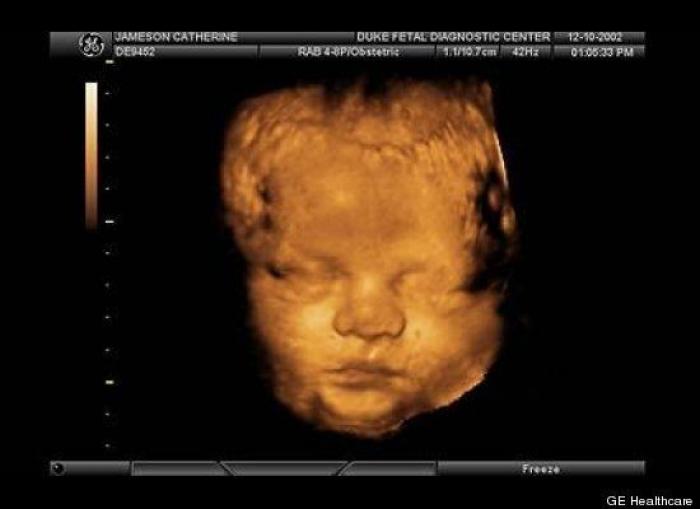

En esta galería puedes ver en fotos como es el desarrollo de un feto de semana en semana:

Desarrollo del feto, en fotos

Ver la galería